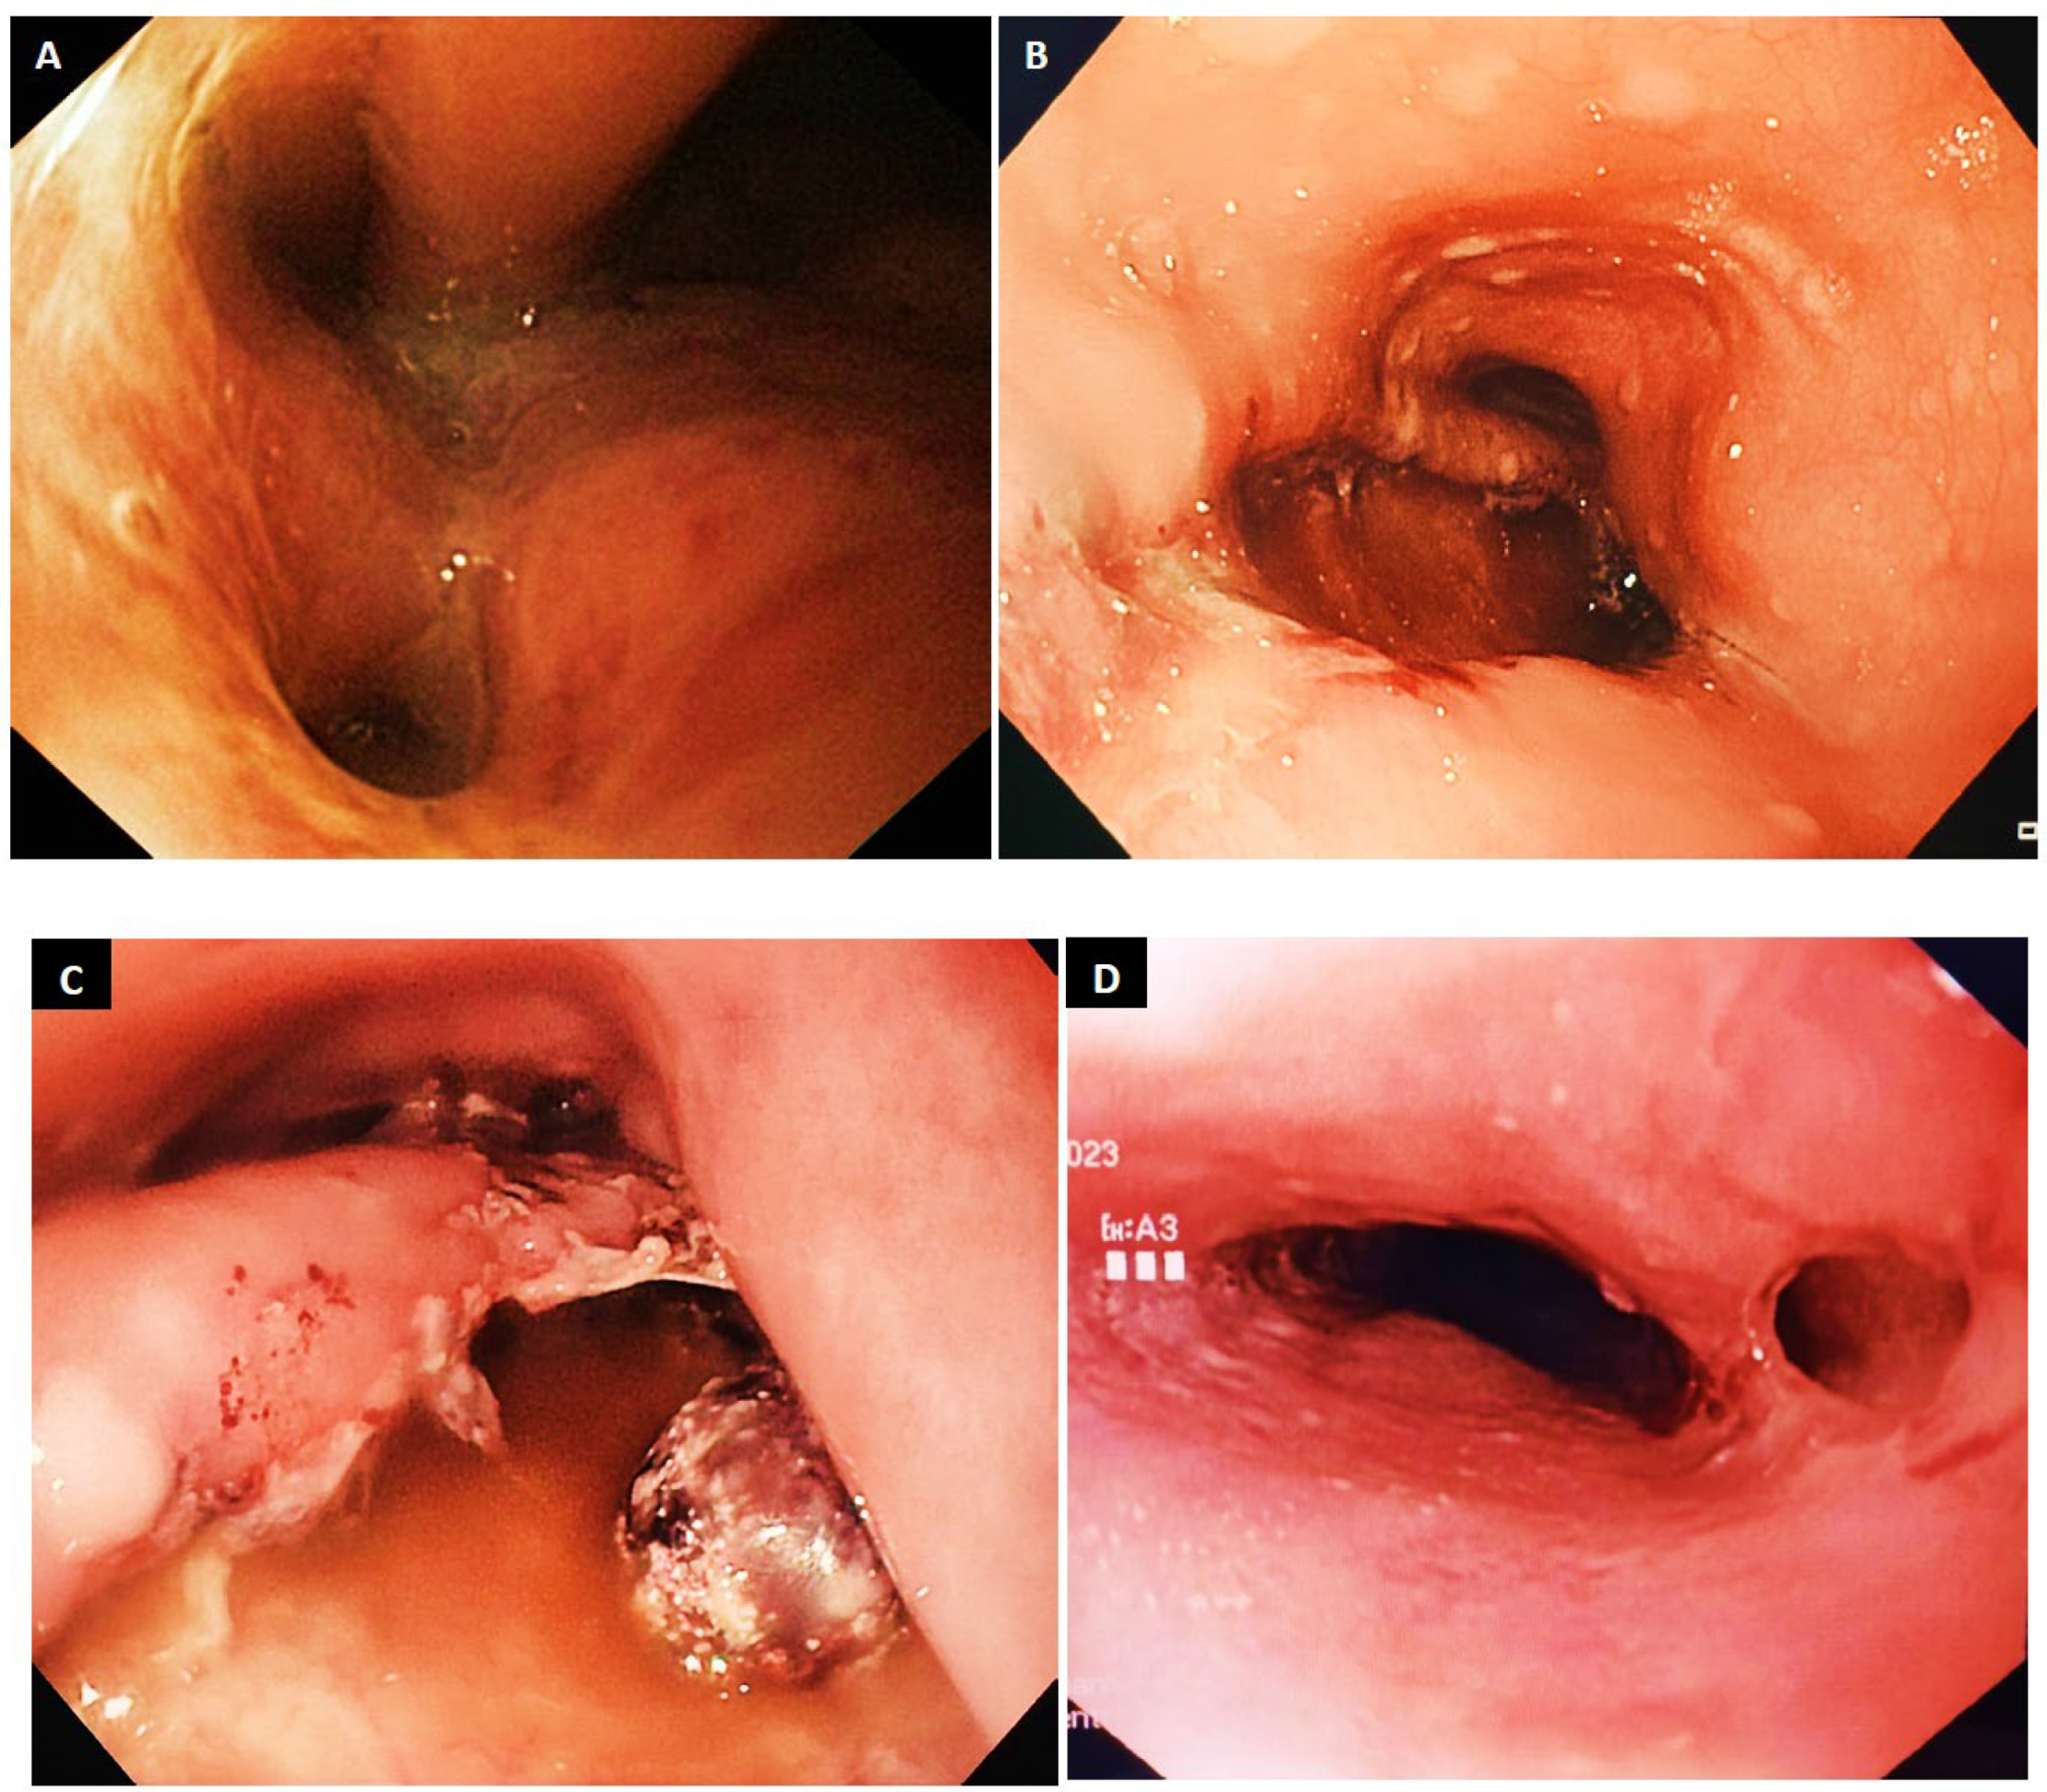

9.3. Clip Placement

9.4. Stent Placement

- Dickinson, K.J.; Buttar, N.; Song, L.M.W.K.; Gostout, C.J.; Cassivi, S.D.; Allen, M.S.; Nichols, F.C.; Shen, K.R.; Wigle, D.A.; Blackmon, S.H. Utility of endoscopic therapy in the management of Boerhaave syndrome. Endosc. Int. Open 2016, 4, E1146–E1150. [Google Scholar] [CrossRef]

- Dickinson, K.J.; Blackmon, S.H. Endoscopic Techniques for the Management of Esophageal Perforation. Oper. Tech. Thorac. Cardiovasc. Surg. 2015, 20, 251–278. [Google Scholar] [CrossRef][Green Version]

- Gurwara, S.; Clayton, S. Esophageal perforations: An endoscopic approach to management. Curr. Gastroenterol. Rep. 2019, 21, 57. [Google Scholar] [CrossRef]

- Cortázar, E.V.; Aguirre, P.A. Endoscopic management of Boerhaave’s syndrome. Rev. Esp. De Enfermedades Dig. 2019, 111, 493. [Google Scholar] [CrossRef]

- JEstorninho, J.; Pimentel, R.; Gravito-Soares, M.; Gravito-Soares, E.; Amaro, P.; Figueiredo, P. Successful Endoscopic Closure of Esophageal Perforation in Boerhaave Syndrome Using the Over-the-Scope Clip. GE-Port. J. Gastroenterol. 2022, 30, 444–450. [Google Scholar] [CrossRef] [PubMed]

- Musala, C.; Eisendrath, P.; Brasseur, A.; Vincent, J.-L.; Cappeliez, S.; Moine, O.; Devière, J.; Lemmers, A. Successful treatment of Boerhaave syndrome with an over-the-scope clip. Endoscopy 2015, 47, E24–E25. [Google Scholar] [CrossRef]

- González-Haba, M.; Ferguson, M.K.; Gelrud, A. Spontaneous esophageal perforation Boerhaave syndrome successfully treated with an over-the-scope clip and fully covered metal stent. Gastrointest. Endosc. 2015, 83, 650. [Google Scholar] [CrossRef] [PubMed]